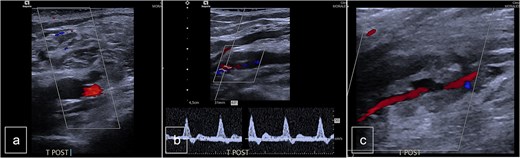

The patient underwent follow-up assessments at 3 weeks and 3 months, which showed an uneventful recovery. Postoperative Doppler sonography demonstrated normal physiological flow (Fig. 4).

Postoperative duplex sonography. (a) Doppler mode. Identification of the PTA. (b) Doppler mode. Triphasic physiological flow in distality of the autologous patch. (c) Doppler mode. Permeability of the PTA.